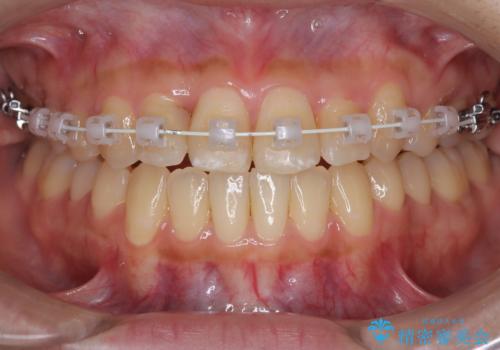

- 患者様は左上の八重歯を気にされて来院されました。八重歯による歯列の乱れだけでなく、翼状捻転(歯がねじれるように生えている状態)も見られました。目立たない矯正を希望されていたため、**インビザライン(マウスピース矯正)**を選択し、左上の小臼歯を抜歯してスペースを作りながら歯を並べる治療計画を立てました。しかし、治療の途中で翼状捻転の改善が十分に進まなかったため、患者様の希望も踏まえ、上顎のみワイヤー矯正に変更することとなりました。

治療開始時はインビザラインを使用し、全体の歯並びを整えながら抜歯スペースを活用して歯を後方へ移動させました。しかし、左上の八重歯のねじれが強く、マウスピースのみでは十分にコントロールできないことが判明。そこで、より細かく歯を動かすために上顎のみワイヤー矯正へ切り替えました。ワイヤー矯正によって翼状捻転も改善し、最終的にバランスの取れた歯並びと噛み合わせを実現。患者様からは「長い治療だったけれど、しっかり整って満足」と嬉しいお言葉をいただきました。